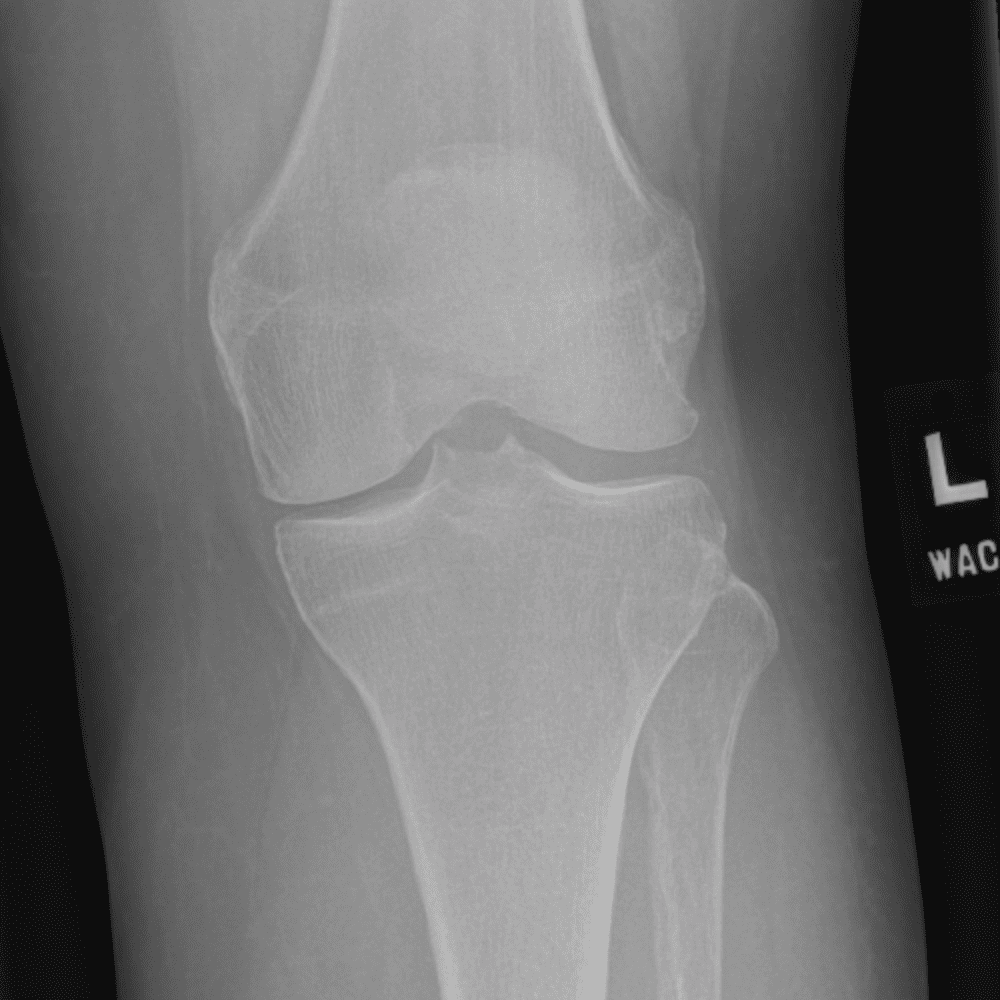

Simula o plantão incluindo casos sutis ou difíceis e alguns normais.